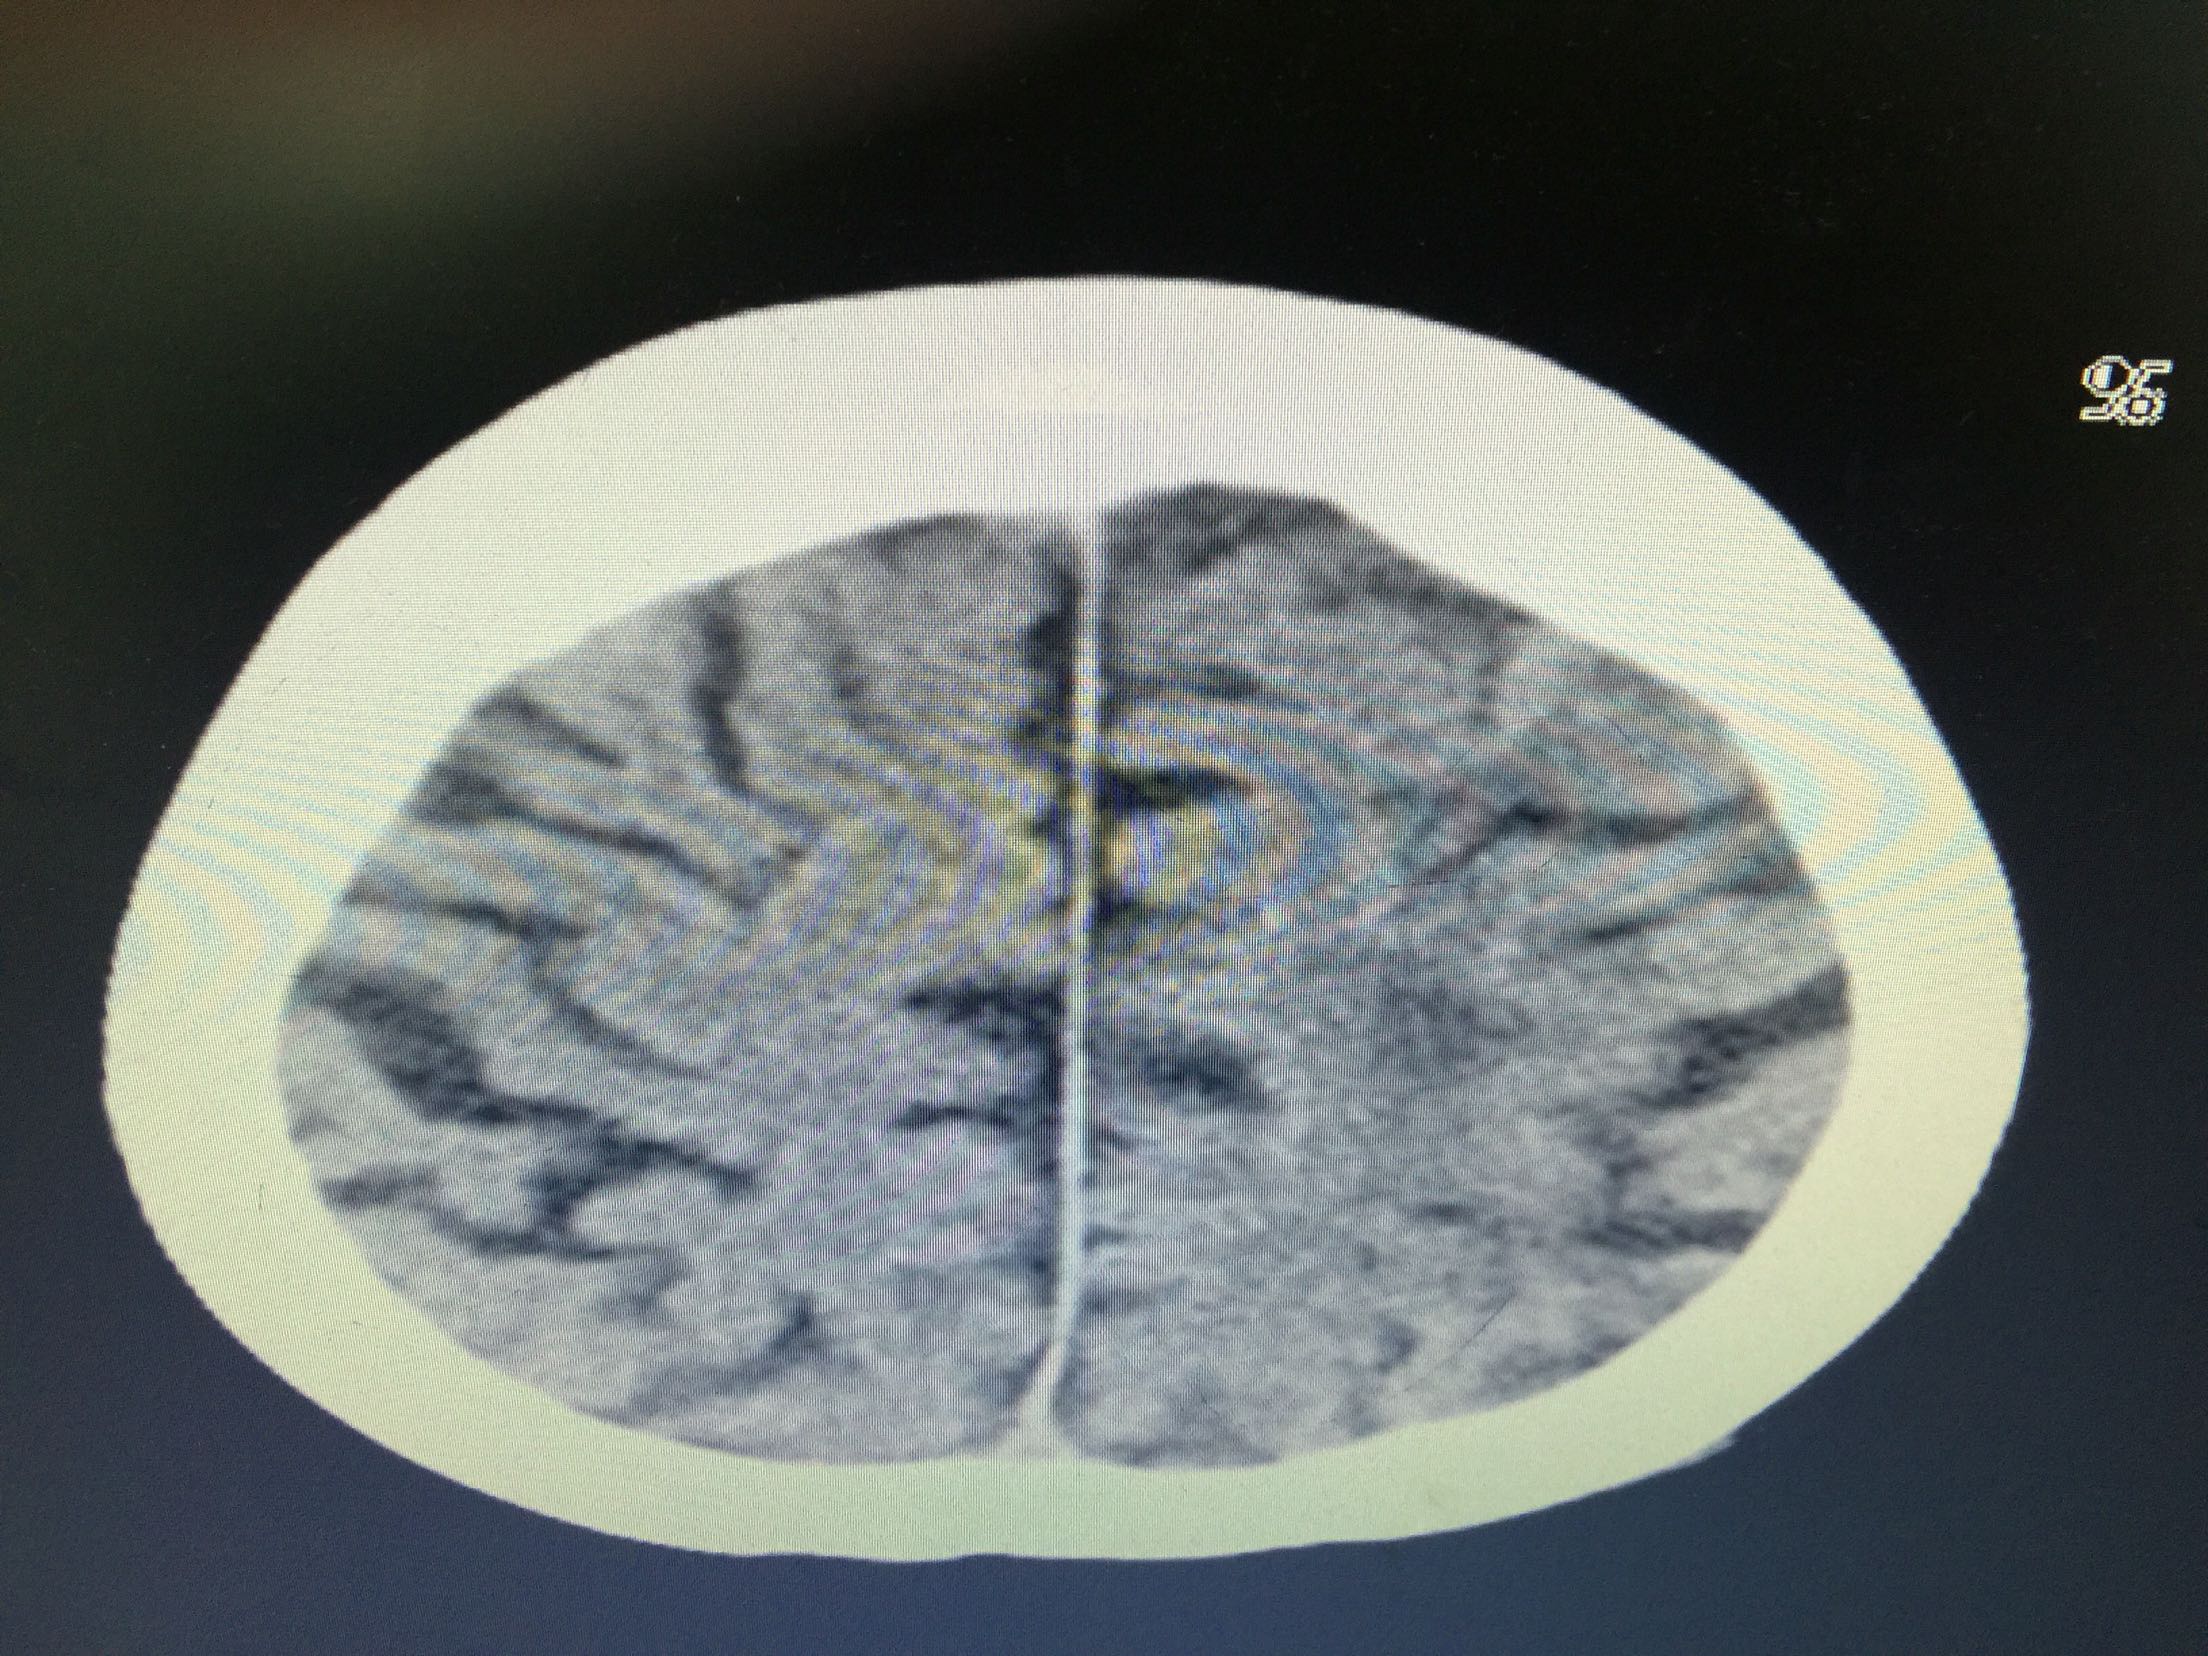

分水岭梗塞1例!

女,86岁,以“嗜睡、右侧肢体无力20小时”入院。 现病史:20小时前无诱因出现嗜睡,可唤醒,问话可答,不理解含义,右侧肢体无力。 既往史:高血压。

查体:血压:136/80mmHg,意识清,不全运动性失语,右侧中枢性面瘫,右侧肢肌力1级,Babinski征左-右+。

诊断:分水岭梗塞! 治疗:扩容、抗板、稳定斑块、促进侧枝建立等治疗。